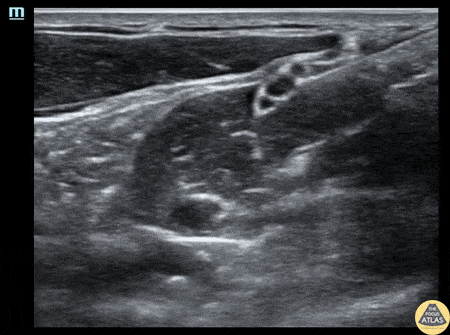

A 20s M with past medical history of prior shoulder dislocations presented with atraumatic shoulder pain and decreased range of motion after he felt a pop while playing sports and reaching across his body. He was found to have an anterior shoulder dislocation without fracture or neurovascular compromise. To facilitate reduction without procedural sedation, an interscalene brachial plexus block was performed. Shown here, the needle enters from the lateral/posterior aspect and the tip is placed adjacent to the brachial plexus, which is seen as 3 hypoechoic circles in a relatively vertical line deep to the sternocleidomastoid muscle. Anesthetic is injected sequentially lateral, deep, medial, and then superficial to the brachial plexus. This patient had relief of pain and his shoulder was able to be reduced at bedside without additional sedation or analgesia. Dr. Larry Benjey, PGY3 Denver Health Residency in Emergency Medicine